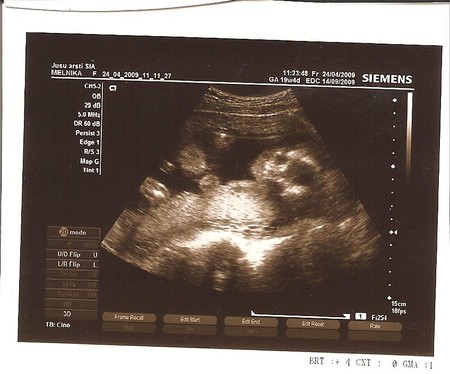

А в остальном, в двух словах, всё у нас ттт в норме, весим мы 790 граммов, по УЗИ срок 25 неделек.Гемоглобин пришёл в норму, давление низковатое (88/55). Есть небольшой тонус, так что придётся пропить но-шпу 10 дней. Лялечка моя лежит вниз головкой, активно дубасит маму ножками в области пупка )))

А вот и наше личико

На папу похожа очень-очень!

заигрывала со мной сегодня, такая смешная! Врач подтвердил, что мы девочки! Ура!